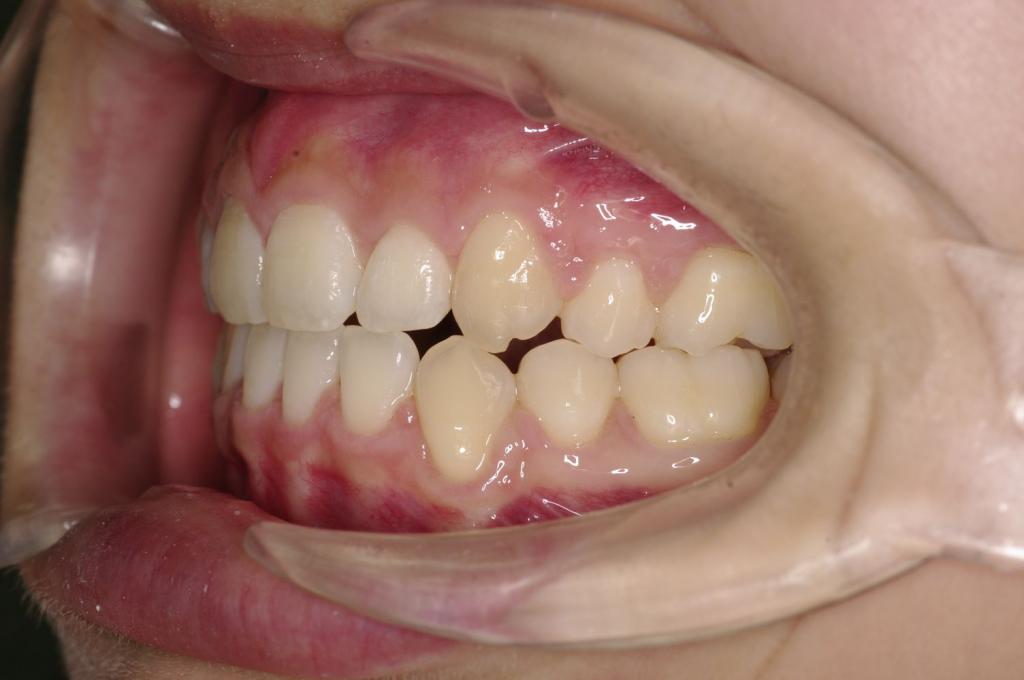

前歯、出っ歯・開咬の矯正治療

(治療期間、治療前後写真、治療方法、費用)WORKS